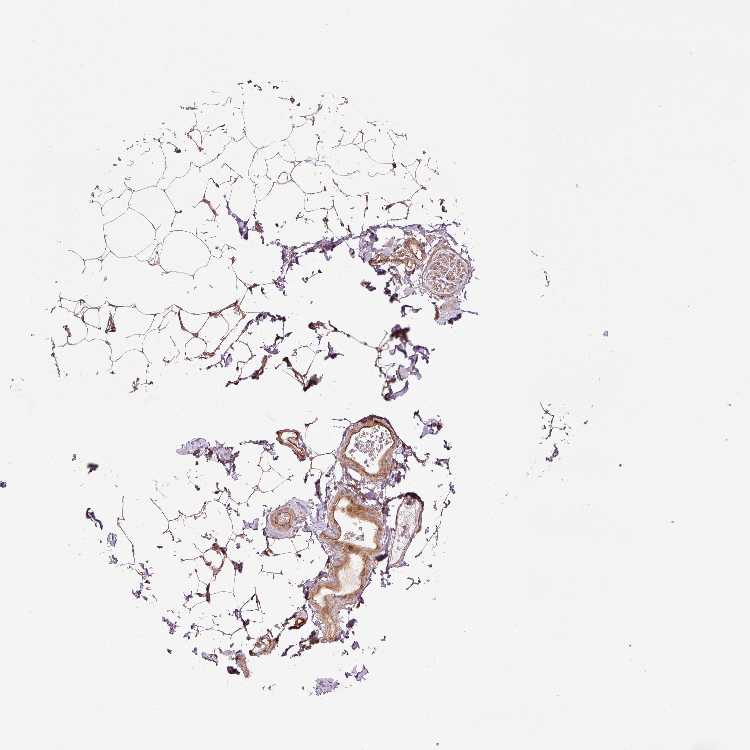

ADIPOSE TISSUE - Antibody stainingi

Antibody staining in the annotated cell types in the current human tissue is reported as not detected, low, medium, or high, based on conventional immunohistochemistry profiling in selected tissues. This score is based on the combination of the staining intensity and fraction of stained cells.

Each image is clickable and will lead to virtual microscopy that enables deeper exploration of all samples and also displays staining intensity scores, fraction scores and subcellular localization as well as patient and tissue information for each sample.

Antibody HPA051433

Adipocytes Medium